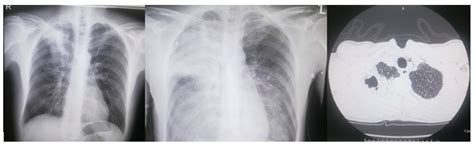

The appearance of pneumonia can vary significantly depending on the causative organism, the patient's immune status, and the timing of the imaging. Generally, radiologists categorize these findings into several distinct patterns:

Cavitation Anaerobes, Staph aureus, TB Lucent area within a consolidation, indicating necrosis.

While identifying pneumonia on CXR is routine, it is not without challenges. Many conditions can mimic the radiographic appearance of pneumonia, leading to potential diagnostic pitfalls. Clinicians must correlate imaging findings with the patient's clinical presentation, physical examination, and laboratory results (such as white blood cell count and inflammatory markers).